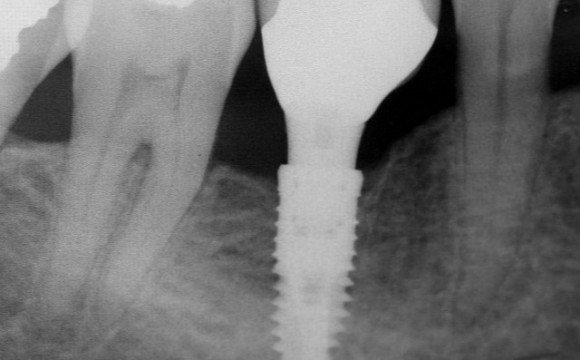

Zubni implantati vam vraćaju osmijeh na lice

Dobro zdravlje usne šupljine itekako je važno. Nakon što izgubimo mliječne zube u djetinjstvu, oni trajni trebali bi nam poslužiti do kraja života. Upravo radi toga, gubitak zuba može biti itekako tr...